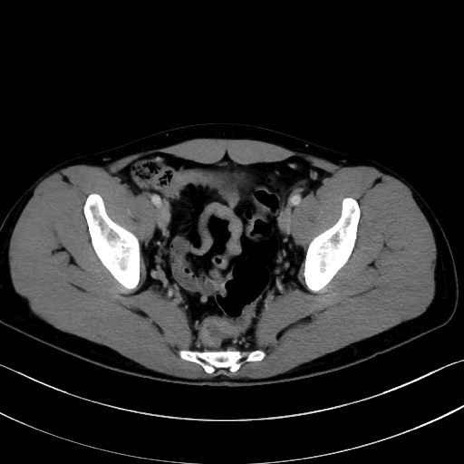

精嚢(seminal vesicle)のCT画像における解剖

症例

【症例】20歳代 男性 スクリーニング